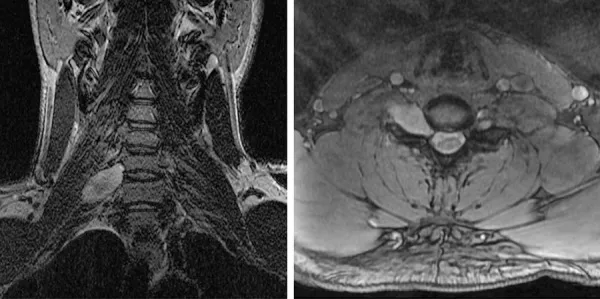

为进一步评估患者,亦进行了脊髓磁共振成像,结果显示右侧C6-7神经孔内有一膨胀性、对比强化的肿块沿C7神经根走行,符合周围神经鞘瘤表现(图4)。左额开颅术后1个月,患者接受了右小脑病变切除术。病理显示为弥漫性星形细胞瘤,由肿瘤性纤维性星形细胞组成,细胞核细长、不规则、深染,浸润于小脑皮层下白质及内颗粒层(图3C)。肿瘤细胞ATRX免疫染色缺失,而包绕其中的非肿瘤性神经元及内皮细胞染色完整,符合ATRX缺失(图3D)。免疫组化检测显示肿瘤细胞IDH1-R132H及组蛋白H3-K27M突变蛋白阴性。Ki67标记指数约5%的肿瘤细胞阳性。诊断为弥漫性星形细胞瘤,WHO II级。考虑到显著的家族史以及存在多种组织学类型不同的脑肿瘤和一处周围神经鞘瘤,建议进行基因组检测。

图4. 颈椎磁共振成像显示髓内硬膜下、髓外肿块,位于右侧C6-C7神经孔中心并沿C7神经根延伸(冠状位T2加权,左图;轴位T1加权增强,右图)。